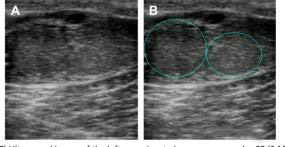

An interesting phenomenon occasionally observed in pre-estrus cows is twin ovulation—where two dominant follicles develop, one on each ovary, or both on the same ovary. If fertilization occurs, the result may be twin pregnancy.

Ultrasound image A and B from a 28-day post-insemination cow using a 6-MHz linear probe at a depth of 4 cm show the left ovary containing two distinct corpora lutea. This confirms that double ovulation occurred during the pre-estrus phase.

Twin pregnancies are more common in high-producing dairy cows and can lead to both economic opportunities and complications (e.g., increased risk of abortion or dystocia). Recognizing twin CLs on ultrasound early helps veterinarians and farmers plan accordingly.